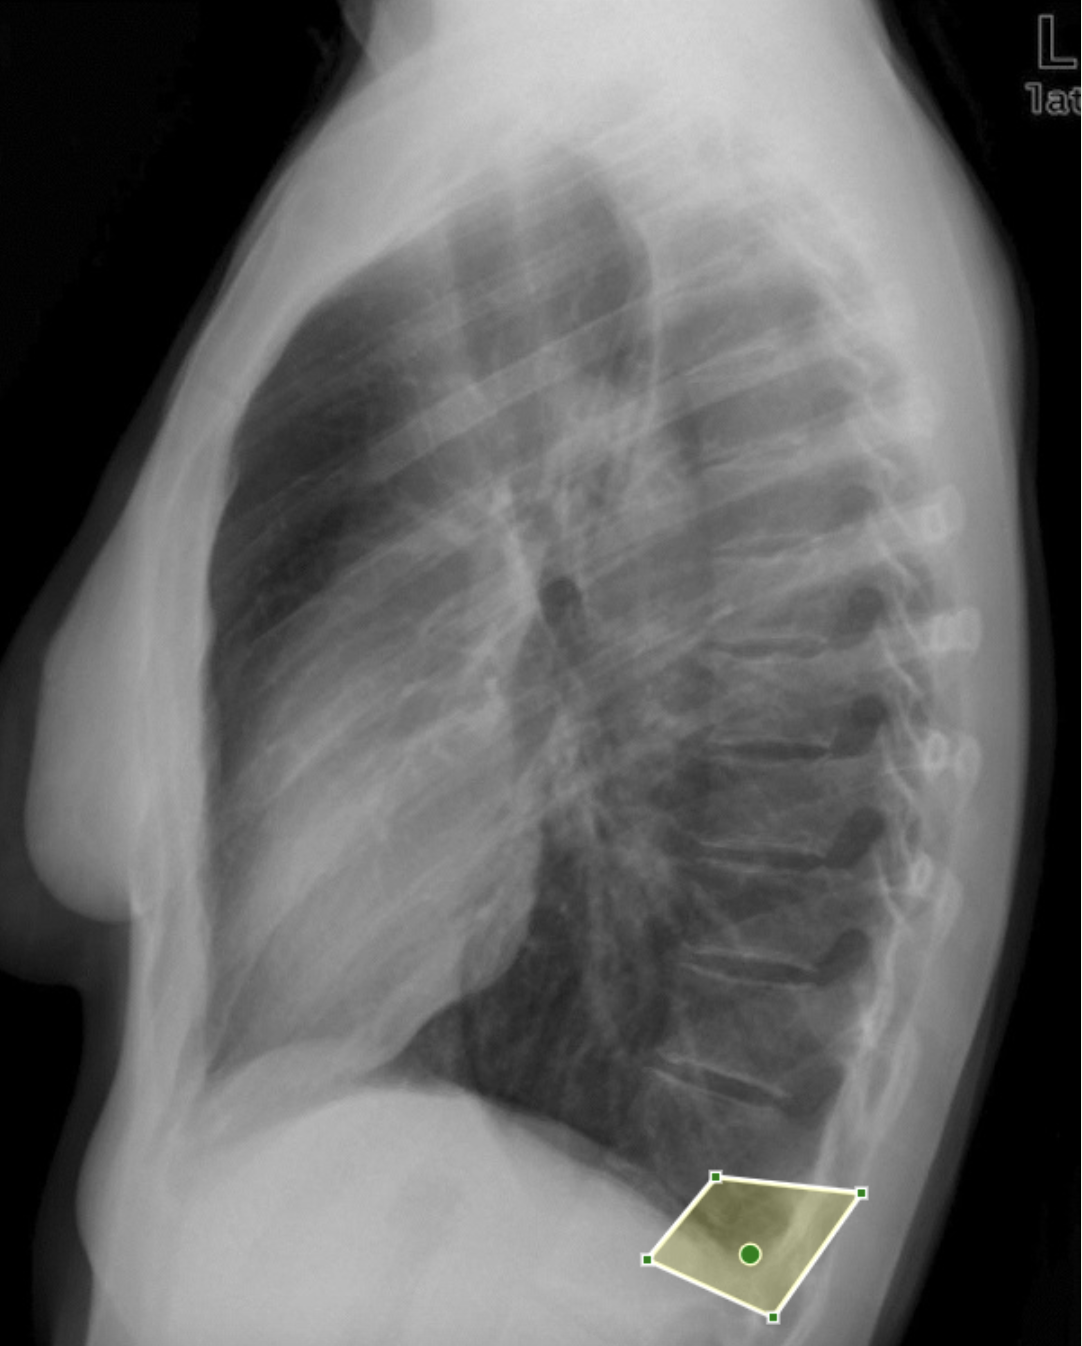

What is shown here?

Posterior costophrenic angle